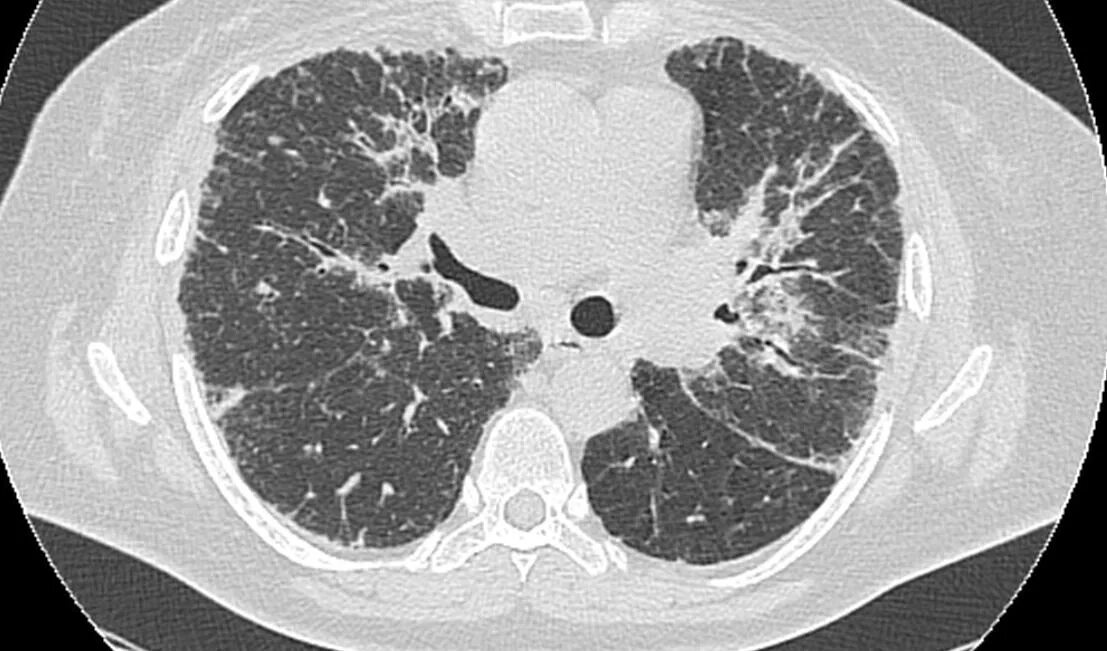

Заболевание кт